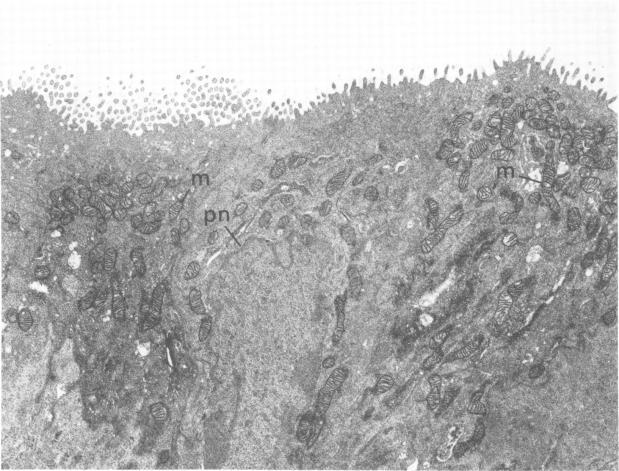

Guinea pig inclusion conjunctivitis, a naturally occurring chlamydial disease of guinea pigs, resolves spontaneously after 3 to 4 weeks. The factors responsible for curbing the infection have not yet been specifically defined. Since Iwata (Invest. Ophthalmol. 15:297-301, 1976) reported cytochemical activity for peroxidase in the conjunctival epithelium of the normal rat, we undertook these studies to determine whether a similar activity exists in the guinea pig, and if so, whether it functions in the elimination of this Chlamydia psittaci infection. Tarsal conjunctivas of 14 normal guinea pigs, 34 infected ones, and 7 control guinea pigs (inoculated with yolk sac only) were excised and tested for peroxidase by the Graham and Karnovsky method (J. Histochem. Cytochem. 14:291-302, 1966). We found that peroxidase activity, virtually absent in normal animals, was intensely stimulated by the infection. This enzymatic activity appeared 2 days after inoculation of the conjunctiva with chlamydia and persisted for 6 to 7 weeks. The enzyme was localized in the rough endoplasmic reticulum and perinuclear cisternae of all layers of the conjunctival epithelium from the external surface to the basal lamina, including cells with no apparent inclusions as well as those heavily parasitized. Reaction in the Golgi complex was variable. No reaction, however, was ever evident in the chlamydial vacuoles or lysosomes, and the organisms continued to grow and multiply during peak enzymatic activity. We therefore concluded that the stimulated enzyme is apparently not directly responsible for the waning of the infection, but instead reflects an alteration of host metabolism that occurs as a consequence of the infection.

豚鼠包涵体结膜炎是豚鼠自然发生的一种衣原体疾病,3至4周后可自发痊愈。抑制感染的因素尚未明确界定。自岩田(《Invest. Ophthalmol.》15:297 - 301,1976年)报道正常大鼠结膜上皮中过氧化物酶具有细胞化学活性以来,我们开展了这些研究,以确定豚鼠是否存在类似活性,若存在,其是否在消除这种鹦鹉热衣原体感染中发挥作用。切除14只正常豚鼠、34只感染豚鼠和7只对照豚鼠(仅接种卵黄囊)的睑结膜,采用格雷厄姆和卡尔诺夫斯基方法(《J. Histochem. Cytochem.》14:291 - 302,1966年)检测过氧化物酶。我们发现,正常动物几乎不存在的过氧化物酶活性在感染后受到强烈刺激。这种酶活性在结膜接种衣原体后2天出现,并持续6至7周。该酶定位于从外表面到基底层的结膜上皮各层的粗面内质网和核周池,包括无明显包涵体的细胞以及严重寄生的细胞。高尔基体中的反应各不相同。然而,衣原体空泡或溶酶体中从未出现明显反应,并且在酶活性高峰期病原体继续生长繁殖。因此,我们得出结论,受刺激的酶显然不是感染减弱的直接原因,而是反映了感染导致的宿主代谢改变。